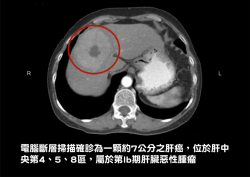

肝腫瘤傳統手術傷口大 微創腹腔鏡助復原快

【焦點時報/記者蔡宗武報導】一名60多歲婦人是B型肝炎帶原患者,因工作繁忙疏於健康檢查,近日經電腦斷層檢查,確診為一顆約7公分的腫瘤。該婦人因有肝硬化之病史,若依傳統手術可能需做擴大肝葉切除手術,但可能造成患者術後肝衰竭,團隊評估為留存術後最大肝體積,先施行肝動脈化學栓塞控制肝癌生長,經減孔洞腹腔鏡手術,身上僅有三個一公分的切口及一個約八公分的下腹比基尼線傷口取出腫瘤,術後恢復...... [閱讀更多]